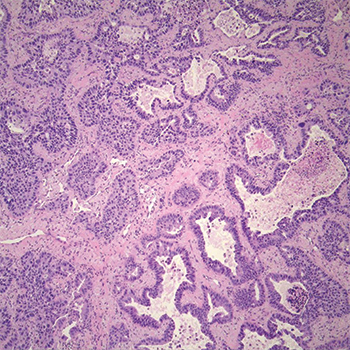

Pathology. Histologic examination showed a moderately differentiated adenocarcinoma, acinar predominant with peripheral lepidic growth (Fig. 1). The tumor measured grossly 2.5 × 2.0 × 1.0 cm, and it extended to but did not invade the visceral pleural. The bronchial, vascular, and parenchymal margins were free of tumor. Lymphatic vessel invasion was identified (Fig. 2) but the 10 lymph nodes examined were negative. Staging was pT1b pN0.